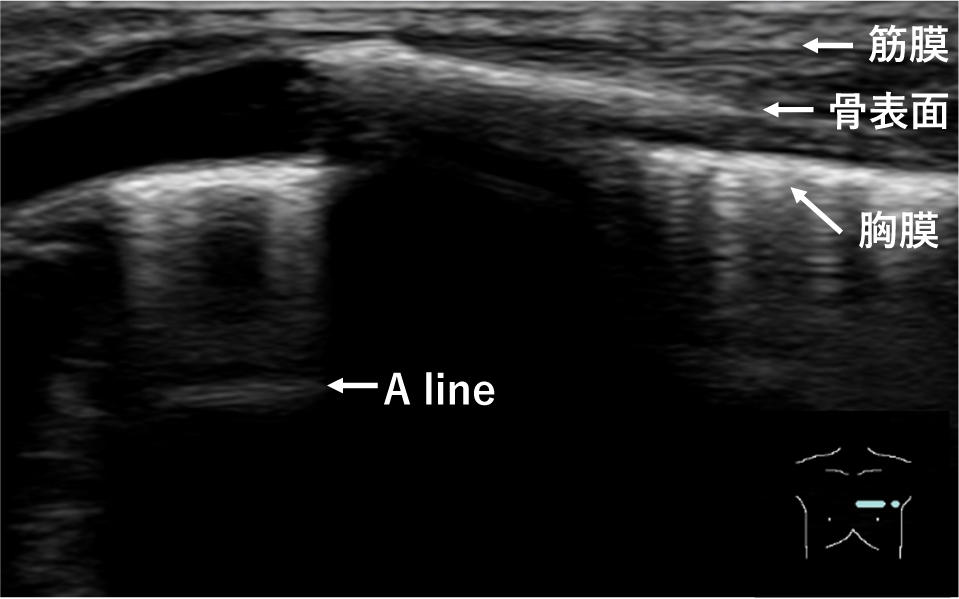

3. 基本走査法3)まずはじめに,プローブは肋骨の走行に直交するように当てる.音響陰影により認識が容易である肋骨をあえて描出し,肋骨の間に,高輝度な線状の胸膜を同定し,観察することが重要である.二つの肋骨を結ぶ線が羽を広げたコウモリのように見えることから,この像はbat signと呼ばれ,呼吸器超音波検査の基本画像となる(Fig.1).肋骨の走行に沿った断面では,胸膜に似た線状高輝度は,筋膜や骨表面,A lineなどさまざま存在する(Fig.2).初学者にとってはbat signのように肋骨をあえて描出することにより,肋骨表面の深さと胸膜面の深さの違いを容易に確認することができるため,胸膜を見誤ることがない.一方で,肋骨があると肋骨の音響陰影により,その深部の情報が得られないため,bat signを見つけ胸膜を同定した後は,プローブを90度回転させ,肋骨の走行に沿った断面でも観察する必要がある.

胸膜に似た線状高輝度は,筋膜や骨表面,A lineなどさまざま存在する.

習熟すればすぐに胸膜を同定できるようになるが,初学者にとっては基本画像であるbat signで胸膜を同定する方が容易である.

健常肺には含気があるため,プローブから発生した超音波は胸膜でほぼ100%反射し,反射波はプローブ面にて,再び反射するといった反射の反復により,多重反射アーチファクトが生じる.これにより,深部に胸膜ラインと平行な線状高輝度が描出され,これをA lineとよぶ(Fig.5).A lineはプローブ面から胸膜ラインまでの距離と等間隔に繰り返し現れ,深部では減衰して見えにくくなる.気胸では壁側胸膜直下が空気でみたされることで超音波が100%反射されるようになることで,A lineはより明瞭に描出される.

プローブからでた超音波は胸膜面でほぼ100%反射し,プローブ面に戻り,再び反射する.この繰り返しにより,多重反射アーチファクトが生じ,深部に胸膜ラインと平行な線状高輝度が描出される.これをA lineと呼ぶ.A lineはプローブ面から胸膜ラインまでの距離と等間隔に繰り返し現れ,深部では減衰して見えにくくなる.